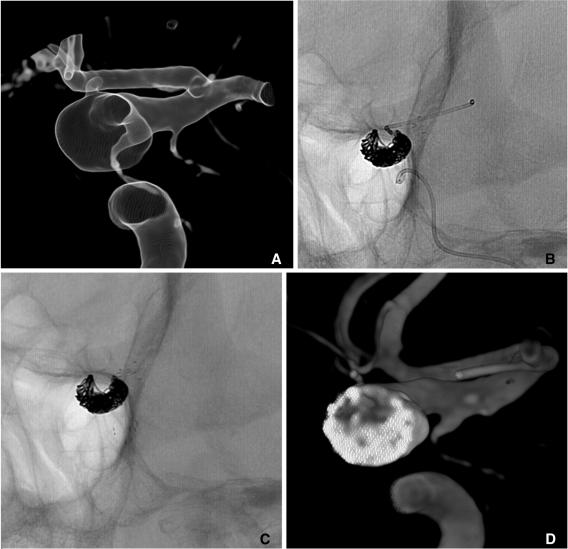

Stent application for the treatment of cerebral aneurysms.

Rapid and striking development in both the techniques and devices make it possible to treat most of cerebral aneurysms endovascularly. Stent has become one of the most important tools in treating difficult aneurysms not feasible for simple coiling. The physical features, the dimensions, and the functional characteristics of the stents show considerable differences. There are also several strategies and tips to treat difficult aneurysms by using stent and coiling. Nevertheless, they require much experience in clinical practice as well as knowledge of the stents to treat cerebral aneurysms safely and effectively. In this report, a brief review of properties of the currently available stents and strategies of their application is presented.

技术和设备的迅速显著发展使得大多数脑动脉瘤能够通过血管内治疗。支架已成为治疗难以单纯栓塞的复杂动脉瘤的最重要工具之一。不同支架的物理特性、尺寸和功能特点存在显著差异。使用支架辅助栓塞治疗复杂动脉瘤也有多种策略和技巧。然而,要安全有效地治疗脑动脉瘤,在临床实践中需要大量经验以及对支架的了解。本报告简要综述了目前可用支架的特性及其应用策略。